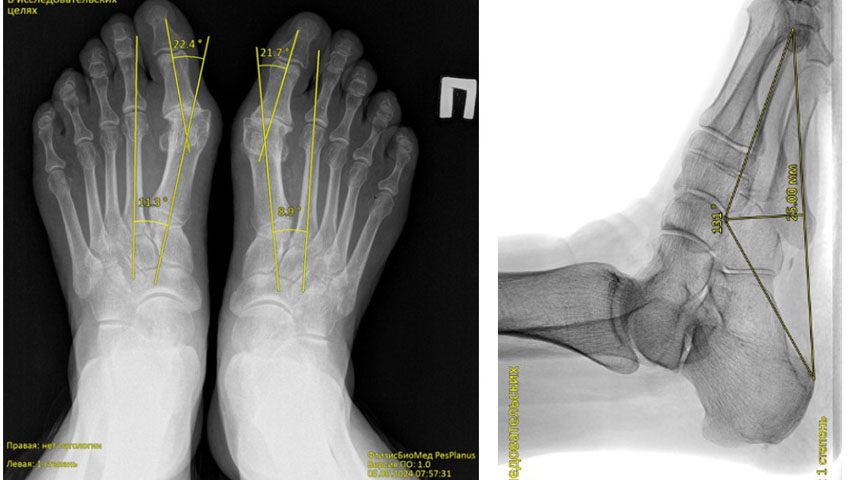

Chương trình phân tích tự động ảnh ‘X-quang bàn chân’ phát hiện bàn chân bẹt dọc và bẹt ngang

FtizisBioMed PesPlanus được phát triển nhằm phân tích tự động hình ảnh X-quang kỹ thuật số của bàn chân, hỗ trợ bác sĩ trong việc:

Phát hiện sớm các dấu hiệu bàn chân bẹt dọc và bẹt ngang;

Giải pháp công nghệ

Chương trình ứng dụng trí tuệ nhân tạo y tế (Medical AI) và các mô hình học máy tiên tiến để phân tích hình ảnh X-quang bàn chân. Hệ thống được huấn luyện trên tập dữ liệu lớn đã được gán nhãn bởi các chuyên gia đầu ngành, đảm bảo độ tin cậy và khả năng tái lập kết quả cao.

Tự động phát hiện và nhận diện nhiều dấu hiệu bệnh lý hình thái bàn chân, hỗ trợ tự động hóa bước đọc phim ban đầu.